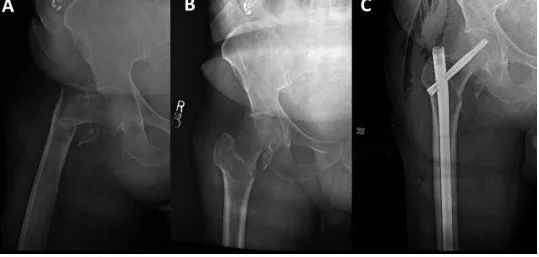

Реверсивные межкарцеральные переломы представляют особые трудности при репозиции и имплантации. Необходимо проводить различие между высокоэнергетическими и низкоэнергетическими переломами вертела, поскольку эти переломы «выглядят» по-разному (изображение ниже). В то время как низкоэнергетические переломы можно успешно лечить с помощью закрытой репозиции на операционном столе, высокоэнергетические переломы часто требуют чрескожной или открытой репозиции.

Боковая рентгеноскопия левого бедра показывает значительное смещение фрагментов перелома, несмотря на адекватную тракцию и ротацию на операционном столе для переломов.